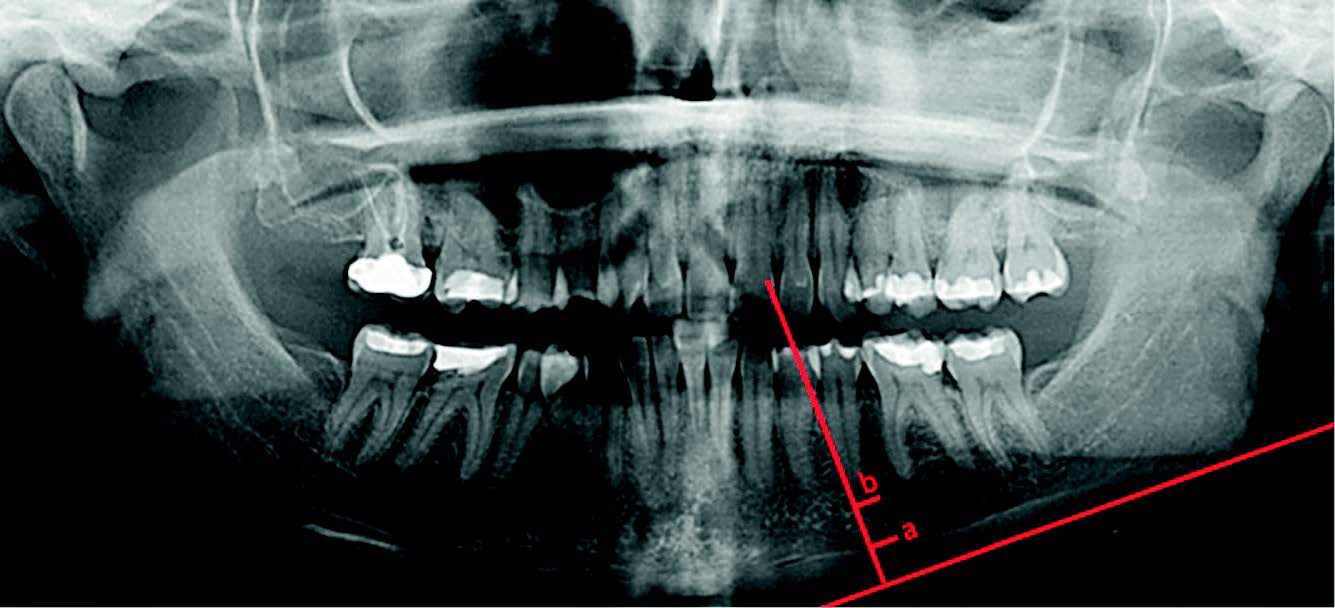

Densité osseuse et radiographie panoramique : incidences orthodontiques

représentation de l’épaisseur corticale mandibulaire (a) et de l’indice mandibulaire (a/b).

Introduction : le panoramique dentaire tient une place prépondérante dans l’investigation radiologique et le diagnostic en orthodontie. Les examens 3D comme le CBCT font office de gold standard dans l’étude de la qualité osseuse mais tous nos cabinets n’en sont pas encore équipés. Par sa simplicité d’utilisation et d’analyse le panoramique dentaire est quant à lui présent dans l’immense majorité de nos cabinets. Par des outils simples applicables sur un cliché panoramique il est possible d’obtenir une évaluation préliminaire de la densité osseuse. C’est dans ce contexte que nous avons souhaité étudier la densité osseuse sur panoramique et en connaître les intérêts dans notre pratique quotidienne.